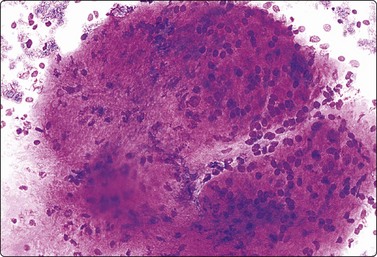

image image

Fig. 7.15 Regenerative epithelial atypia in mastitis

(A) Atypical, reactive/regenerating epithelial cells with a background of histiocytes, inflammatory cells and debris (MGG, HP); (B) Corresponding tissue section (H&E, IP).